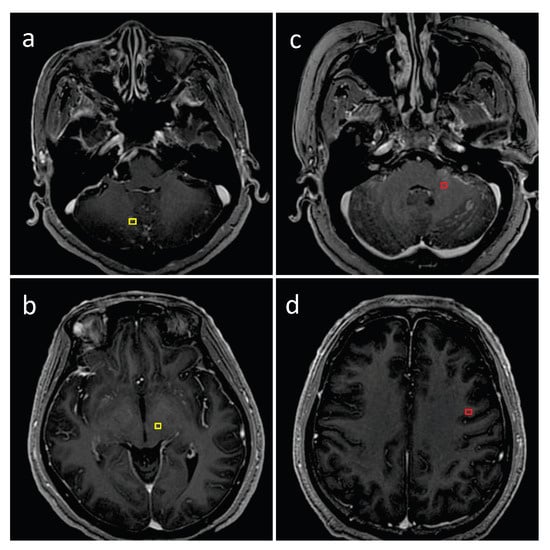

2.3. Dataset Ground Truth

2.4. Image Preprocessing